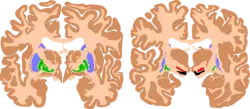

| The basal ganglia plays essential roles in voluntary motor function. Various forms of damage to the basal ganglia can cause a range of movement disorders. | |

Like other forms of CP, it si primarily associated with damage to the basal ganglia in the form of lesions that occur during brain development due to bilirubin encephalopathy and hypoxic–ischemic brain injury.[7]

CP in general is a non-progressive, neurological condition that results from brain injury and malformation occurring before cerebral development is complete.[3] ADCP is associated with injury and malformations to the extrapyramidal tracts in the basal ganglia or the cerebellum.[7] Lesions to this region principally arise via hypoxic ischemic brain injury or bilirubin encephalopathy.[7]

Hypoxic-ischemic brain injury is a form of cerebral hypoxia in which oxygen cannot perfuse to cells in the brain. Lesions in the putamen and thalamus caused by this type of brain injury are primary causes of ADCP and can occur during the prenatal period and shortly after.[7] Lesions that arise after this period typically occur as a result of injury or infections of the brain.[18]

Bilirubin encephalopathy, also known as kernicterus, is the accumulation of bilirubin in the grey matter of the central nervous system. The main accumulation targets of hyperbilirubinemia are the basal ganglia, ocular movement nucleus, and acoustic nucleus of the brainstem.[7] Pathogenesis of bilirubin encephalopathy involves several factors, including the transport of bilirubin across the blood–brain barrier and into neurons.[7] Mild disruption results in left cognition impairment, while severe disruption results in ADCP.[7] Lesions caused by accumulation of bilirubin occur mainly in the global pallidus and hypothalamus.[7] Disruption of the blood–brain barrier by disease or a hypoxic ischemic injury can also contribute to an accumulation of bilirubin in the brain.[7] Bilirubin encephalopathy leading to cerebral palsy has been greatly reduced by effective monitoring and treatment for hyperbilirubinemia in preterm infants.[7] As kernicterus has decreased due to improvements in care, over the last 50 years the proportion of children developing athetoid CP has decreased.[19] In most cases, will have normal intelligence.

Multiple classification systems using magnetic resonance imaging (MRI) have been developed, linking brain lesions to time of birth, cerebral palsy subtype and functional ability.[23][24][25][26] Around 70% of patients with DCP show lesions in the cortical and deep grey matter of the brain, more specifically in the basal ganglia and thalamus. However, other brain lesions and even normal-appearing MRI findings can occur, for example white matter lesions and brain maldevelopments.[2][25][27][28] Patients with pure basal ganglia and thalamus lesions are more likely to show more severe choreoathetosis whereas dystonia may be associated with other brain lesions, such as the cerebellum.[2] These lesions occur mostly during the peri- and postnatal period since these regions have a high vulnerability during the late third trimester of the pregnancy.[29] Unfortunately, contemporary imaging is not sophisticated enough to detect all subtle brain deformities and network disorders in dystonia. Research with more refined imaging techniques including diffusion tensor imaging and functional MRI is required.[10][30]